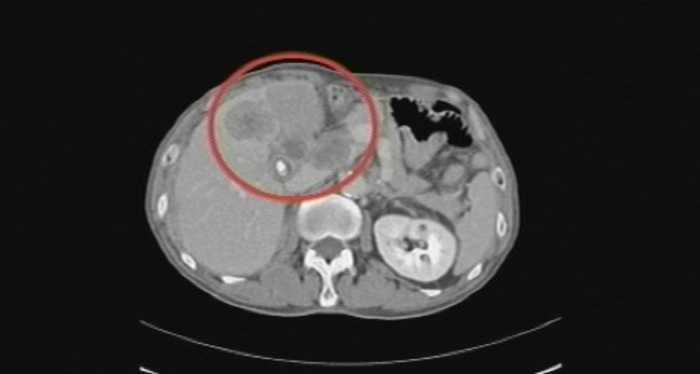

이유 없이 소화 안 됐는데 담낭암? 담낭암 초기 증상

특별한 이유 없이 소화가 계속 안 되고 얼굴이 누레진다면 조심해야 한다.

단순히 스트레스나 피로로 인한 증상이 아니라, 담낭암이나 담도암이 원인일 수 있다.

국가암등록통계에 따르면 담낭·담도암은 국내 많이 발생하는 10대 암 중 8번째에 해당하지만, 5년 상대생존율은 29%에 불과해 치료가 쉽지 않은 암이다. 모두 초기에는 특별한 증상이 없어 조기 발견이 어렵기 때문이다.

가려움증은 담도가 막혀 담즙이 정체되면서 알레르기를 유발하는 특정 물질이 발생하면서 생기고, 황달은 종양이 담도에서 십이지장으로 이어지는 부분을 폐쇄해 담즙의 흐름을 막으면서 혈액 내 빌리루빈 수치가 과다해져 발생한다. 이때 가려움증은 주로 밤에 발생하고 긁어도 시원하지 않은 기분이 드는 것이 특징이다. 그러나 가려움증은 피부질환으로 인한 것이라 생각하기 쉽고, 황달은 암이 서서히 진행되면서 나중에 나타나기 때문에 앞선 증상이 있다고 해서 암을 의심하기란 어렵다. 이 때문에 대개 소화불량이나 복통으로 인해 검사를 받다가 발견되는 경우가 많다.